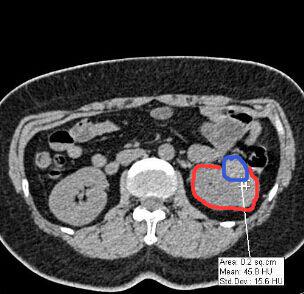

相信很多人和筆者一樣,還是感到疑惑,傳統(tǒng)拍片和3D打印出來的器官模型具體有哪些不同,后者又如何表示病變或者需要進行手術(shù)的位置呢?對于這一點,專業(yè)進行3D設(shè)計和打印的東莞創(chuàng)客聯(lián)盟公司給讀者解答了這個疑惑。其負責(zé)人陳小姐表示,通過不同顏色來表達病變或需要進行手術(shù)的位置,所打印出器官模型足以讓病變位置一目了然。為便于說明,其負責(zé)人展示他們做的一個案例:

某醫(yī)院的外科醫(yī)生需要做一個3D腎臟模型,但CT片拍出的二維圖像中,其腫瘤位置只是通過灰色的色階來表示(臨床應(yīng)用中稱之為CT值),如上圖中紅色圈出來的是腎臟截面,藍色則為腫瘤位置。從圖中可以看出,在CT片子中藍色部分僅僅比紅色部分要白一點。